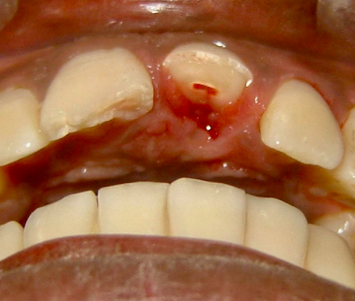

complicated crown fracture

-enamel-dentin-pulp

-apply concept 1: if root mature then remove the pulp/RCT, if root immature then preserve radicular pulp tissue